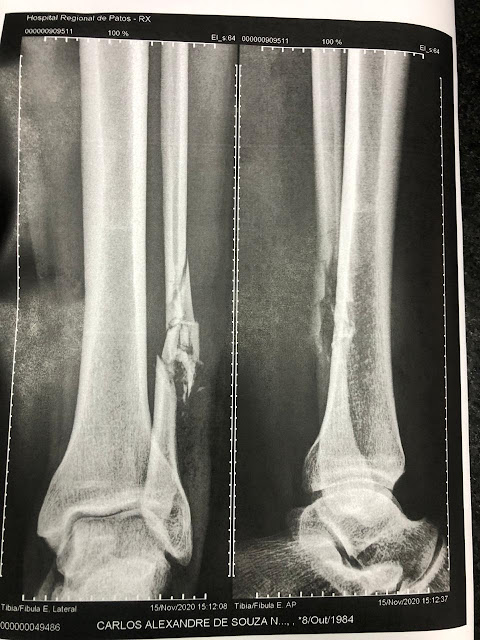

Osso fraturado.